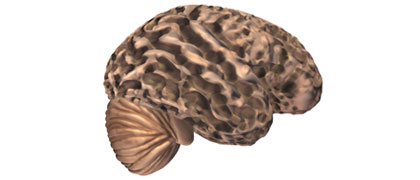

Lippincott Williams & Wilkins. Reproduced with permission from Neurosurgery 1998; 43(4): 877-8.